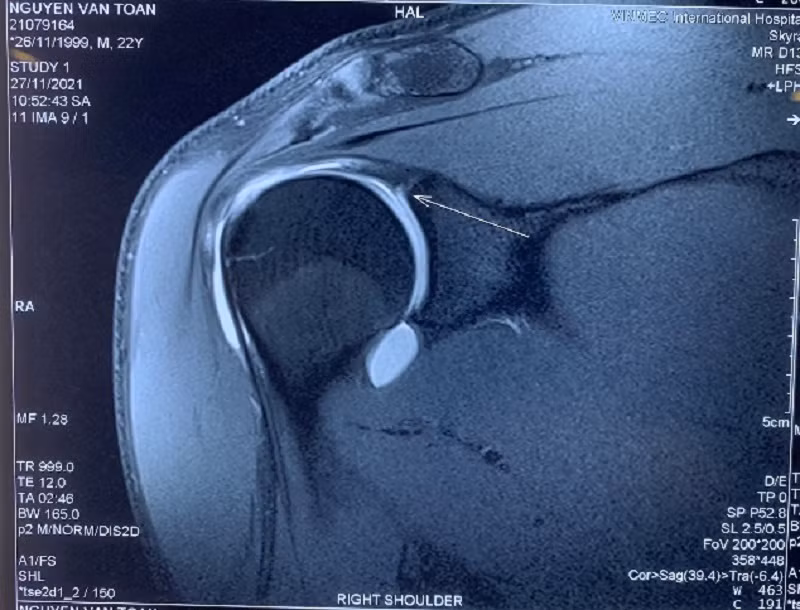

Để chẩn đoán tổn thương này, không thể dùng X-quang hoặc chụp CT mà phải sử dụng chụp MRI có thuốc cản quang để quan sát rõ được các vết rách tại vị trí bám của gân nhị đầu, tránh bỏ sót tổn thương.

Phim MRI chưa có tiêm thuốc cản quang hình ảnh tổn thương không thật điển hình.

Qua phim chụp MRI cản quang và thăm khám lâm sàng, GS Dũng cùng các bác sĩ đã đưa ra kết luận Văn Toản bị chấn thương cơ nhị đầu, cụ thể là bị tổn thương một phần chân bám của cơ nhị đầu cũng như sụn viền chỗ chảo khớp vai.

Phim MRI khi có tiêm thuốc thấy rõ tổn thương hơn.